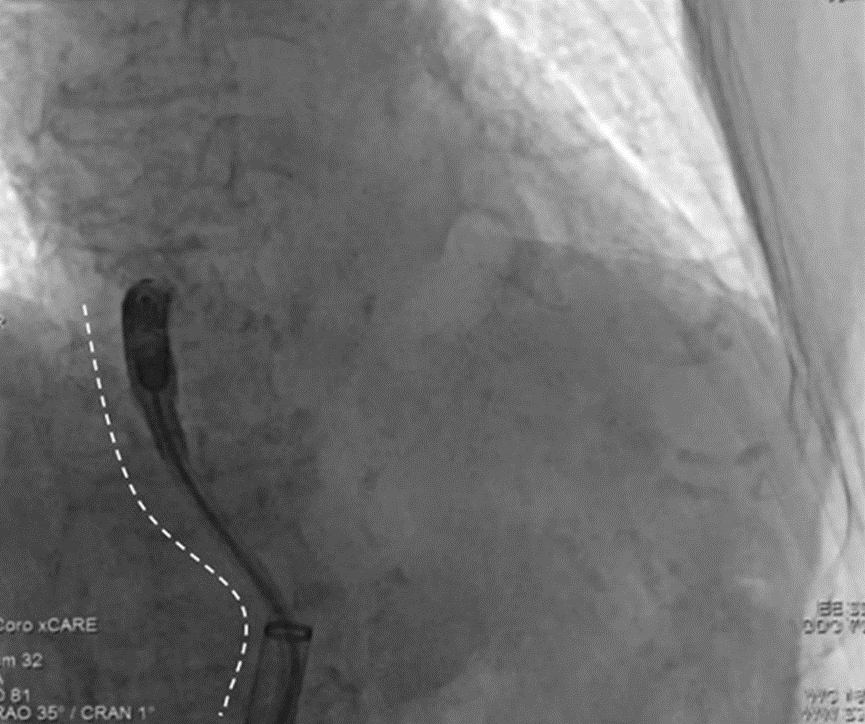

由于患者下腔静脉与肝静脉交界处存在明显的角度(图1),导管系统在体内推进非常困难。

图1:右前斜位(RAO 30°)透视显示输送路径存在明显角度(虚线所示)